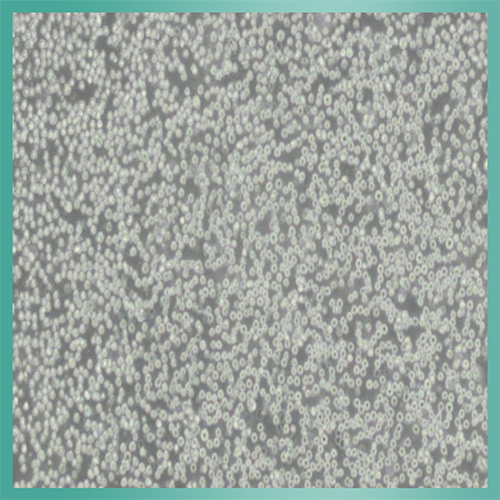

EL4细胞_小鼠淋巴瘤细胞背景描述:EL4细胞是从用9,10-二甲基-1,2-苯并蒽在C57BL小鼠中诱导中建立的。EL-4细胞能抗0.1mM氢化可的松,对20mcg/ml PHA敏感。EL-4细胞还有一个亚株(EL4.IL-2)可以生成高水平的IL-2。

生长特性:悬浮细胞

细胞形态:淋巴母细胞样